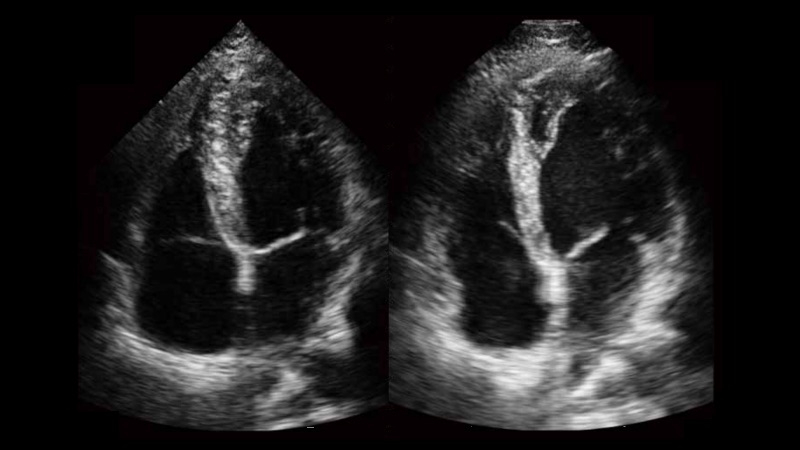

With WideScan, the ultrasound image can be enlarged when performing a real time scan by using linear, convex or phased array probe, for a more complete view of large lesions or anatomic structures.